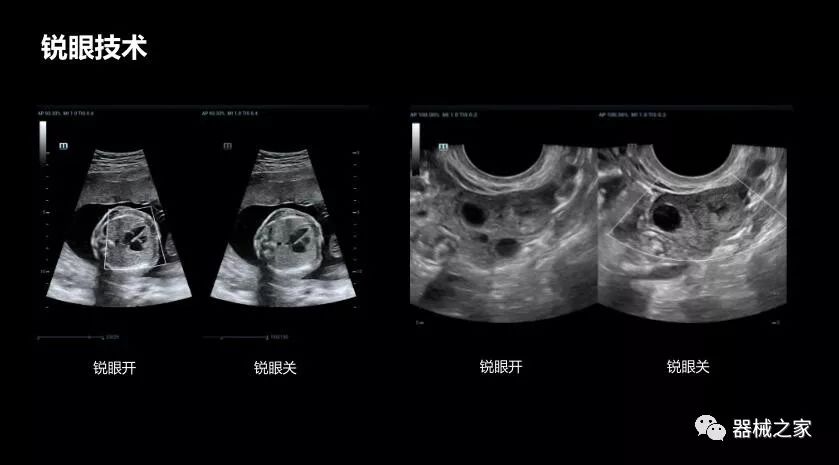

銳眼技術

做胎兒心臟檢查的時候,如果是聲窗不好的孕婦,很難看清胎兒心腔 。女媧Resona 8的銳眼技術能很好的優化心腔內的噪聲,讓胎心結構完美的呈現。